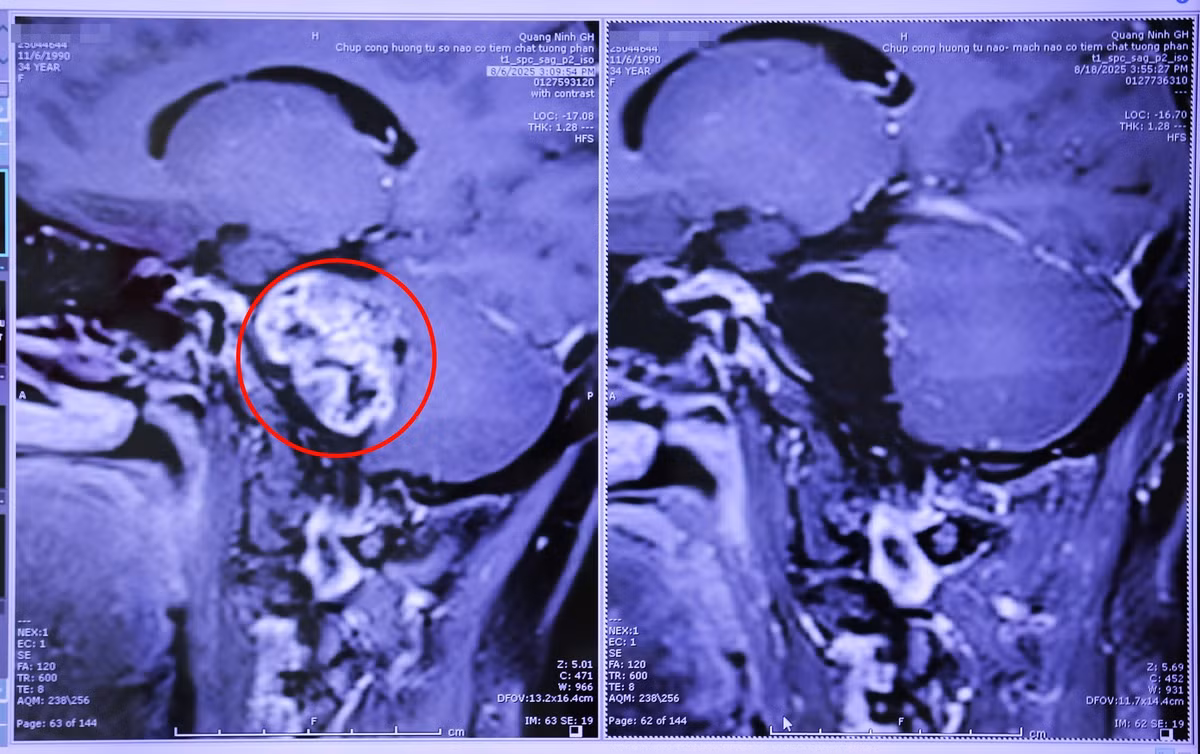

Một trường hợp khác có khối u cùng vị trí là bệnh nhân T.H.N (35 tuổi, phường Cẩm Phả, tỉnh Quảng Ninh) thường xuyên đau đầu, chóng mặt, đi lại khó khăn. Đến khám tại bệnh viện, kết quả chụp cắt lớp vi tính phát hiện 1 khối u dây thần kinh số 8 bên phải, kích thước 30x40mm, chèn ép thân não và tiểu não và các dây thần kinh sọ.

Với sự hỗ trợ của chuyên gia, kíp bác sĩ ngoại thần kinh đã thực hiện phẫu thuật lấy u thành công qua kính vi phẫu, ứng dụng hệ thống cảnh báo thần kinh trong mổ hiện đại, giúp lấy bỏ toàn bộ khối u dây thần kinh và bảo tồn cấu trúc giải phẫu các dây thần kinh.

u-nao-2.jpg

Hình ảnh chụp cộng hưởng từ khối u dây thần kinh số 8 được phẫu thuật lấy bỏ toàn bộ - Ảnh BVCC